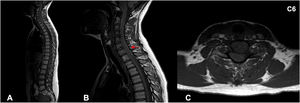

Nervous system involvement is uncommon in granulomatosis with polyangiitis (GPA), a systemic autoimmune disease with episodes of necrotizing vasculitis. It is usually due to the compressive effect of dural or epidural masses. Spinal hemorrhagic presentation is exceptional. A 41-year-old woman diagnosed with GPA presented with three episodes of acute spinal subdural hematoma separated by eight years and ten months, respectively. The symptomatic debut was pain and paresis in all episodes. On all occasions, a lesion compatible with acute spinal subdural hematoma was diagnosed by magnetic resonance imaging (MRI). All episodes were treated conservatively with corticosteroids and immunosuppressants. The patient presented complete neurological recovery in the first two episodes. A mild residual left lower limb paresis remains after the last one. Follow-up MRI was performed after all episodes, and no focal intraspinal lesions were detected. Spinal subdural hemorrhage is a form of manifestation of GPA, either as a debut or in the course of the disease. We describe the third confirmed case of spontaneous spinal hemorrhage secondary to GPA published in the literature and the first with recurrence. Given the extraordinary response to immunosuppressive therapy, a high level of clinical suspicion is necessary to establish treatment as early as possible.

Presentamos un caso en una paciente diagnosticada de granulomatosis con poliangeitis (GPA) que presentó en dos ocasiones separadas por un lapso de 8 años, hematoma subdural agudo espinal con diferentes niveles de afectación en cada uno de los episodios. Se añade una revisión de la literatura. Una mujer de 48 años diagnosticada de GPA, presentó tres episodios de hematoma subdural espinal agudo; separados por un período de tiempo en primer lugar de 8 años y en segundo lugar de 10 meses. Clínicamente, las tres veces se manifestaron con dolor y paresia. En todas las ocasiones, se diagnosticó mediante Resonancia Magnética Nuclear (RMN) la presencia de una lesión compatible con hematoma subdural espinal agudo. Todos los episodios se trataron de forma conservadora con corticoesteroides y Rituximab. La paciente presentó recuperación neurológica completa en los dos primeros episodios. En relación al último; presenta una paresia leve en miembro inferior izquierdo. En todos los episodios se realizó control por RMN y no se detectaron alteraciones intraespinales. La hemorragia subdural espinal es una posible forma de manifestación de la GPA, bien como debut o en el curso de la enfermedad. Es necesario un alto nivel de sospecha clínica para establecer el tratamiento de la forma más precoz posible. Presenta una respuesta extraordinaria a la terapia inmunosupresora. Es posible una recuperación completa a través del tratamiento conservador. Recomendamos un abordaje combinado.